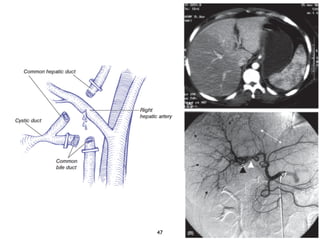

Anatomia del hilio hepático

• Sistema portal: posterior

• Arterias: anteriores, pasan a la Izq. de la bifurcación

• 82% Art. Derecha cruza posterior

• 13% una art. cruza por delante VB. Izq

• Conductos biliares: epiportales

• 56% Derecho e Izquierdo

• ángulo de unión 45-90 grados

• 16% se trifurca

10